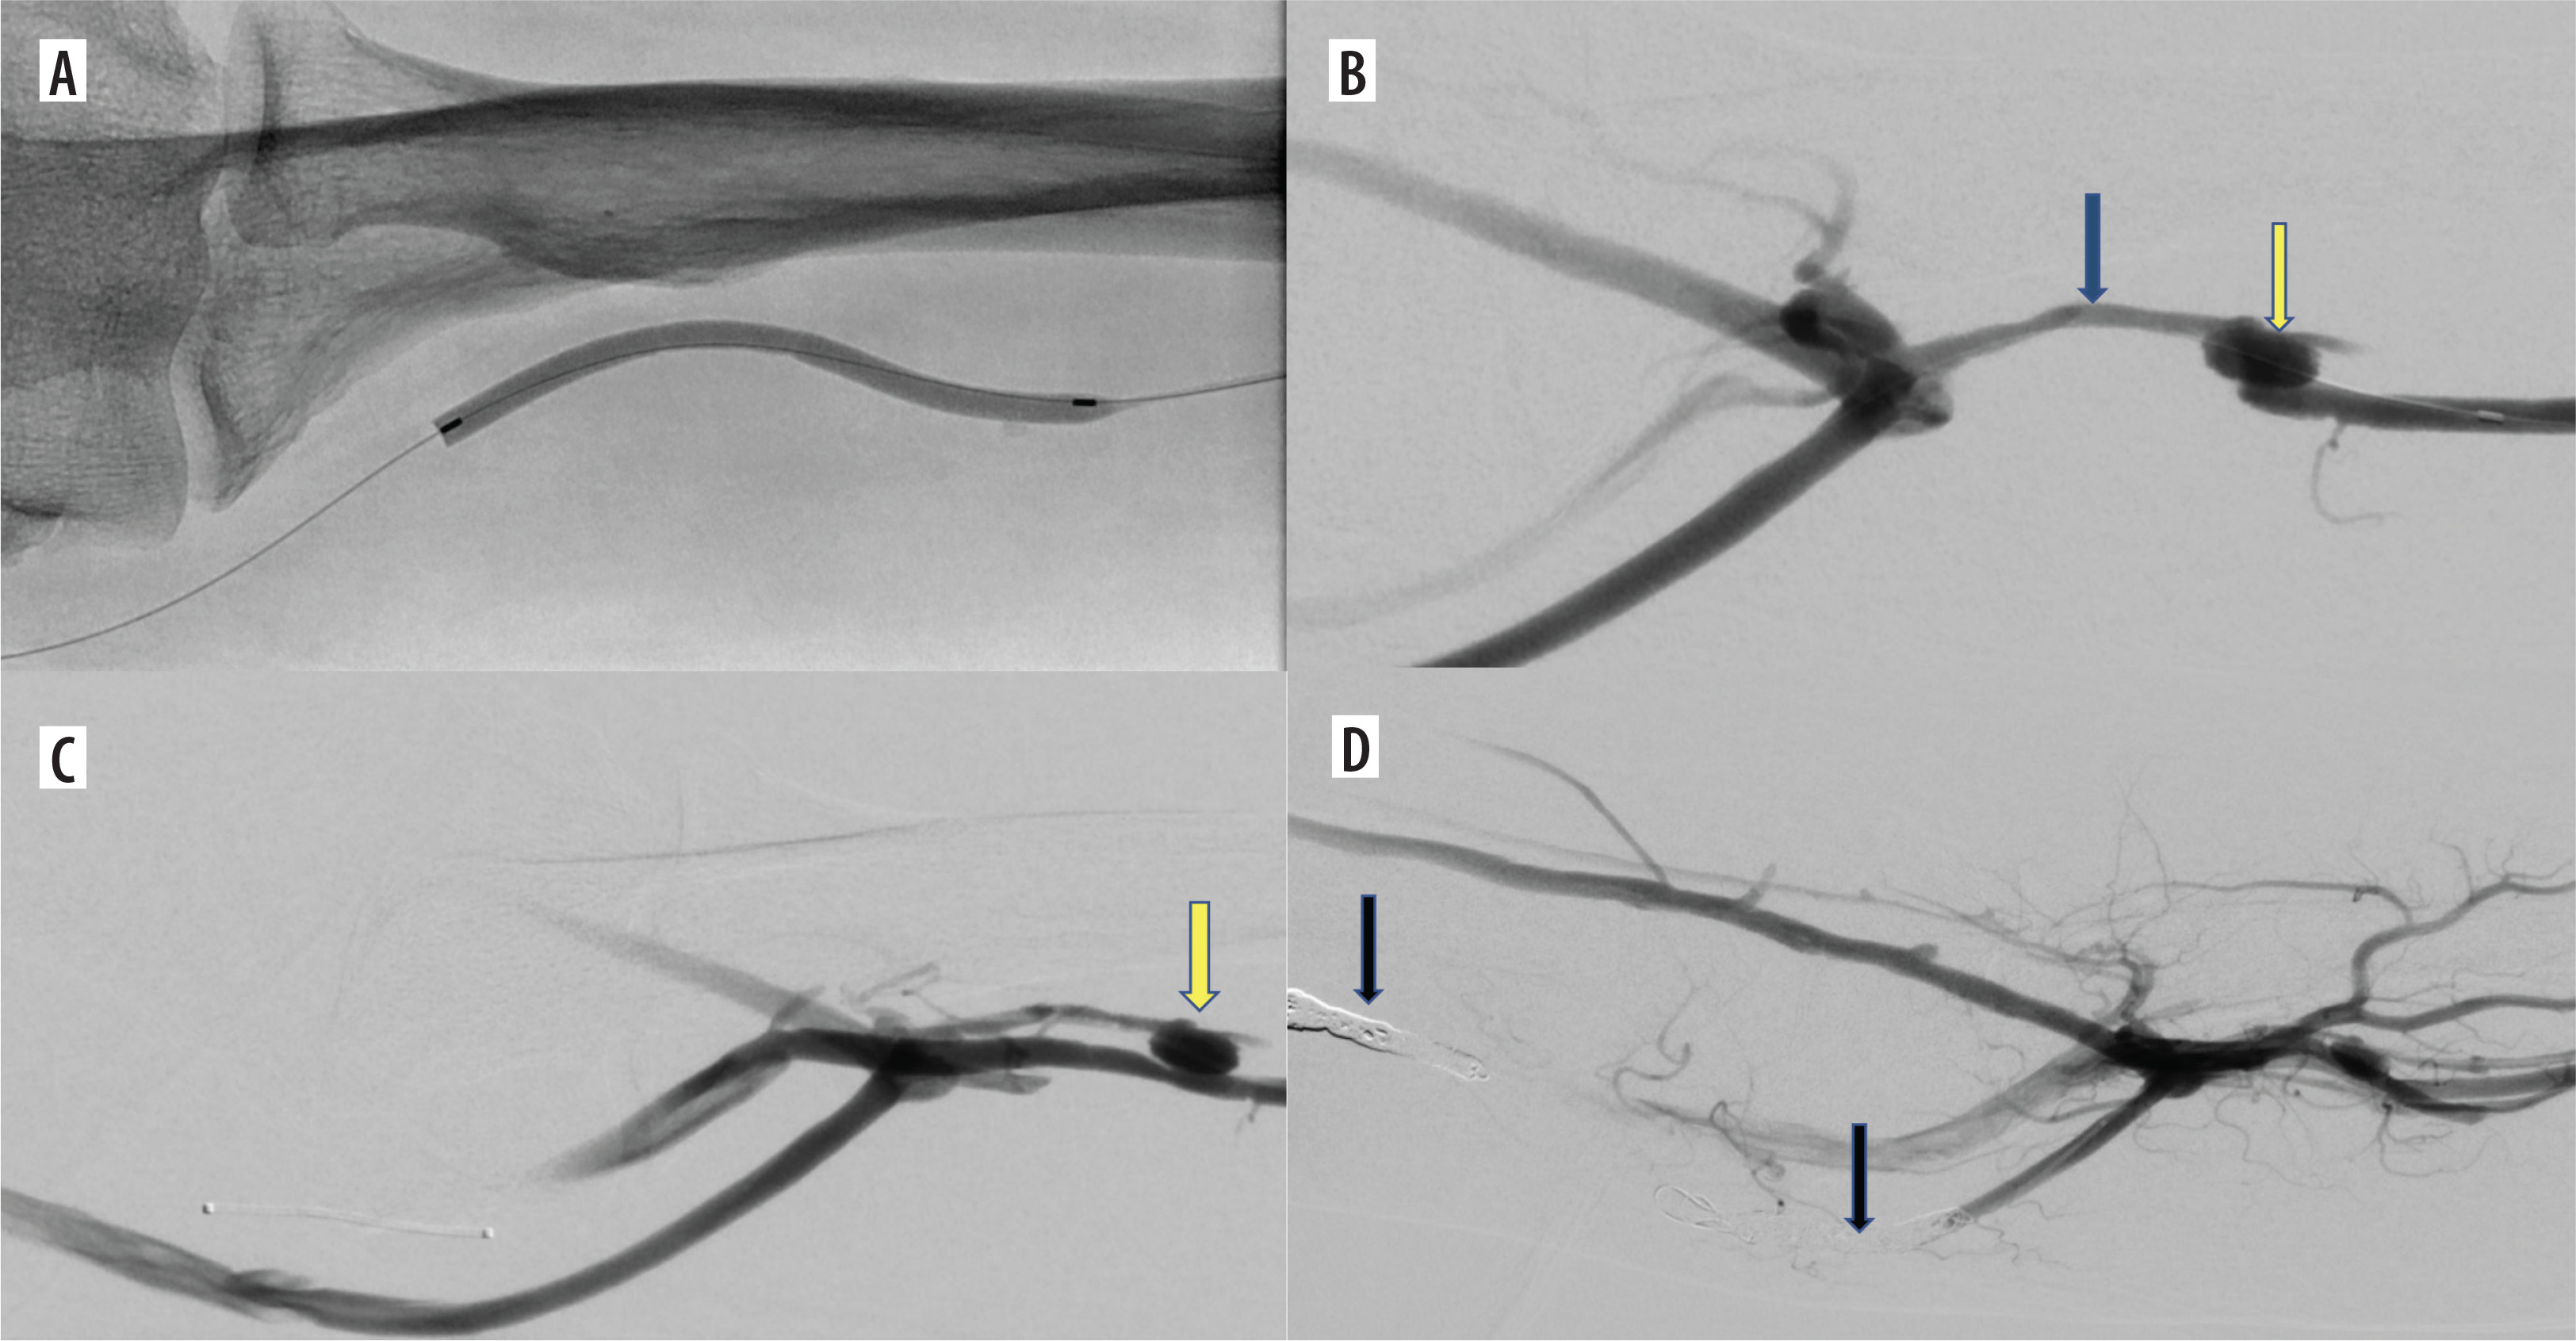

Figure 2

Additional intravascular procedures performed concurrently with endoAVF creation. A) Balloon angioplasty of the radial vein with vasospasm. B) Outcome of balloon angioplasty of the radial vein between the arteriovenous anastomosis and the perforating vein (yellow arrow – arterio-venous anastomosis, blue arrow – radial vein between arteriovenous anastomosis and perforating vein). C) Blood outflow from the arteriovenous fistula manly into the brachial and basilic veins (yellow arrow – arterio-venous anastomosis). D) Embolization of brachial and basilic veins (arrows) – increased blood flow through the cephalic vein